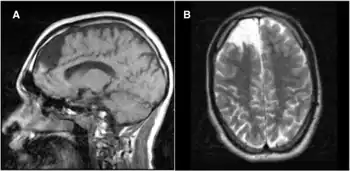

a)Individual with propionic acidemia (and neuropsychiatric manifestations) shows right frontal lobe encephalomalacia in sagittal b) and axial scans

Elevated metabolites of propionic acid (for example, 3-hydroxypropionate, methylcitrate, tiglylglycine, propionylglycine) found in blood and urine along with normal biotinidase levels.[7]